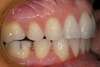

Vues avant le traitement